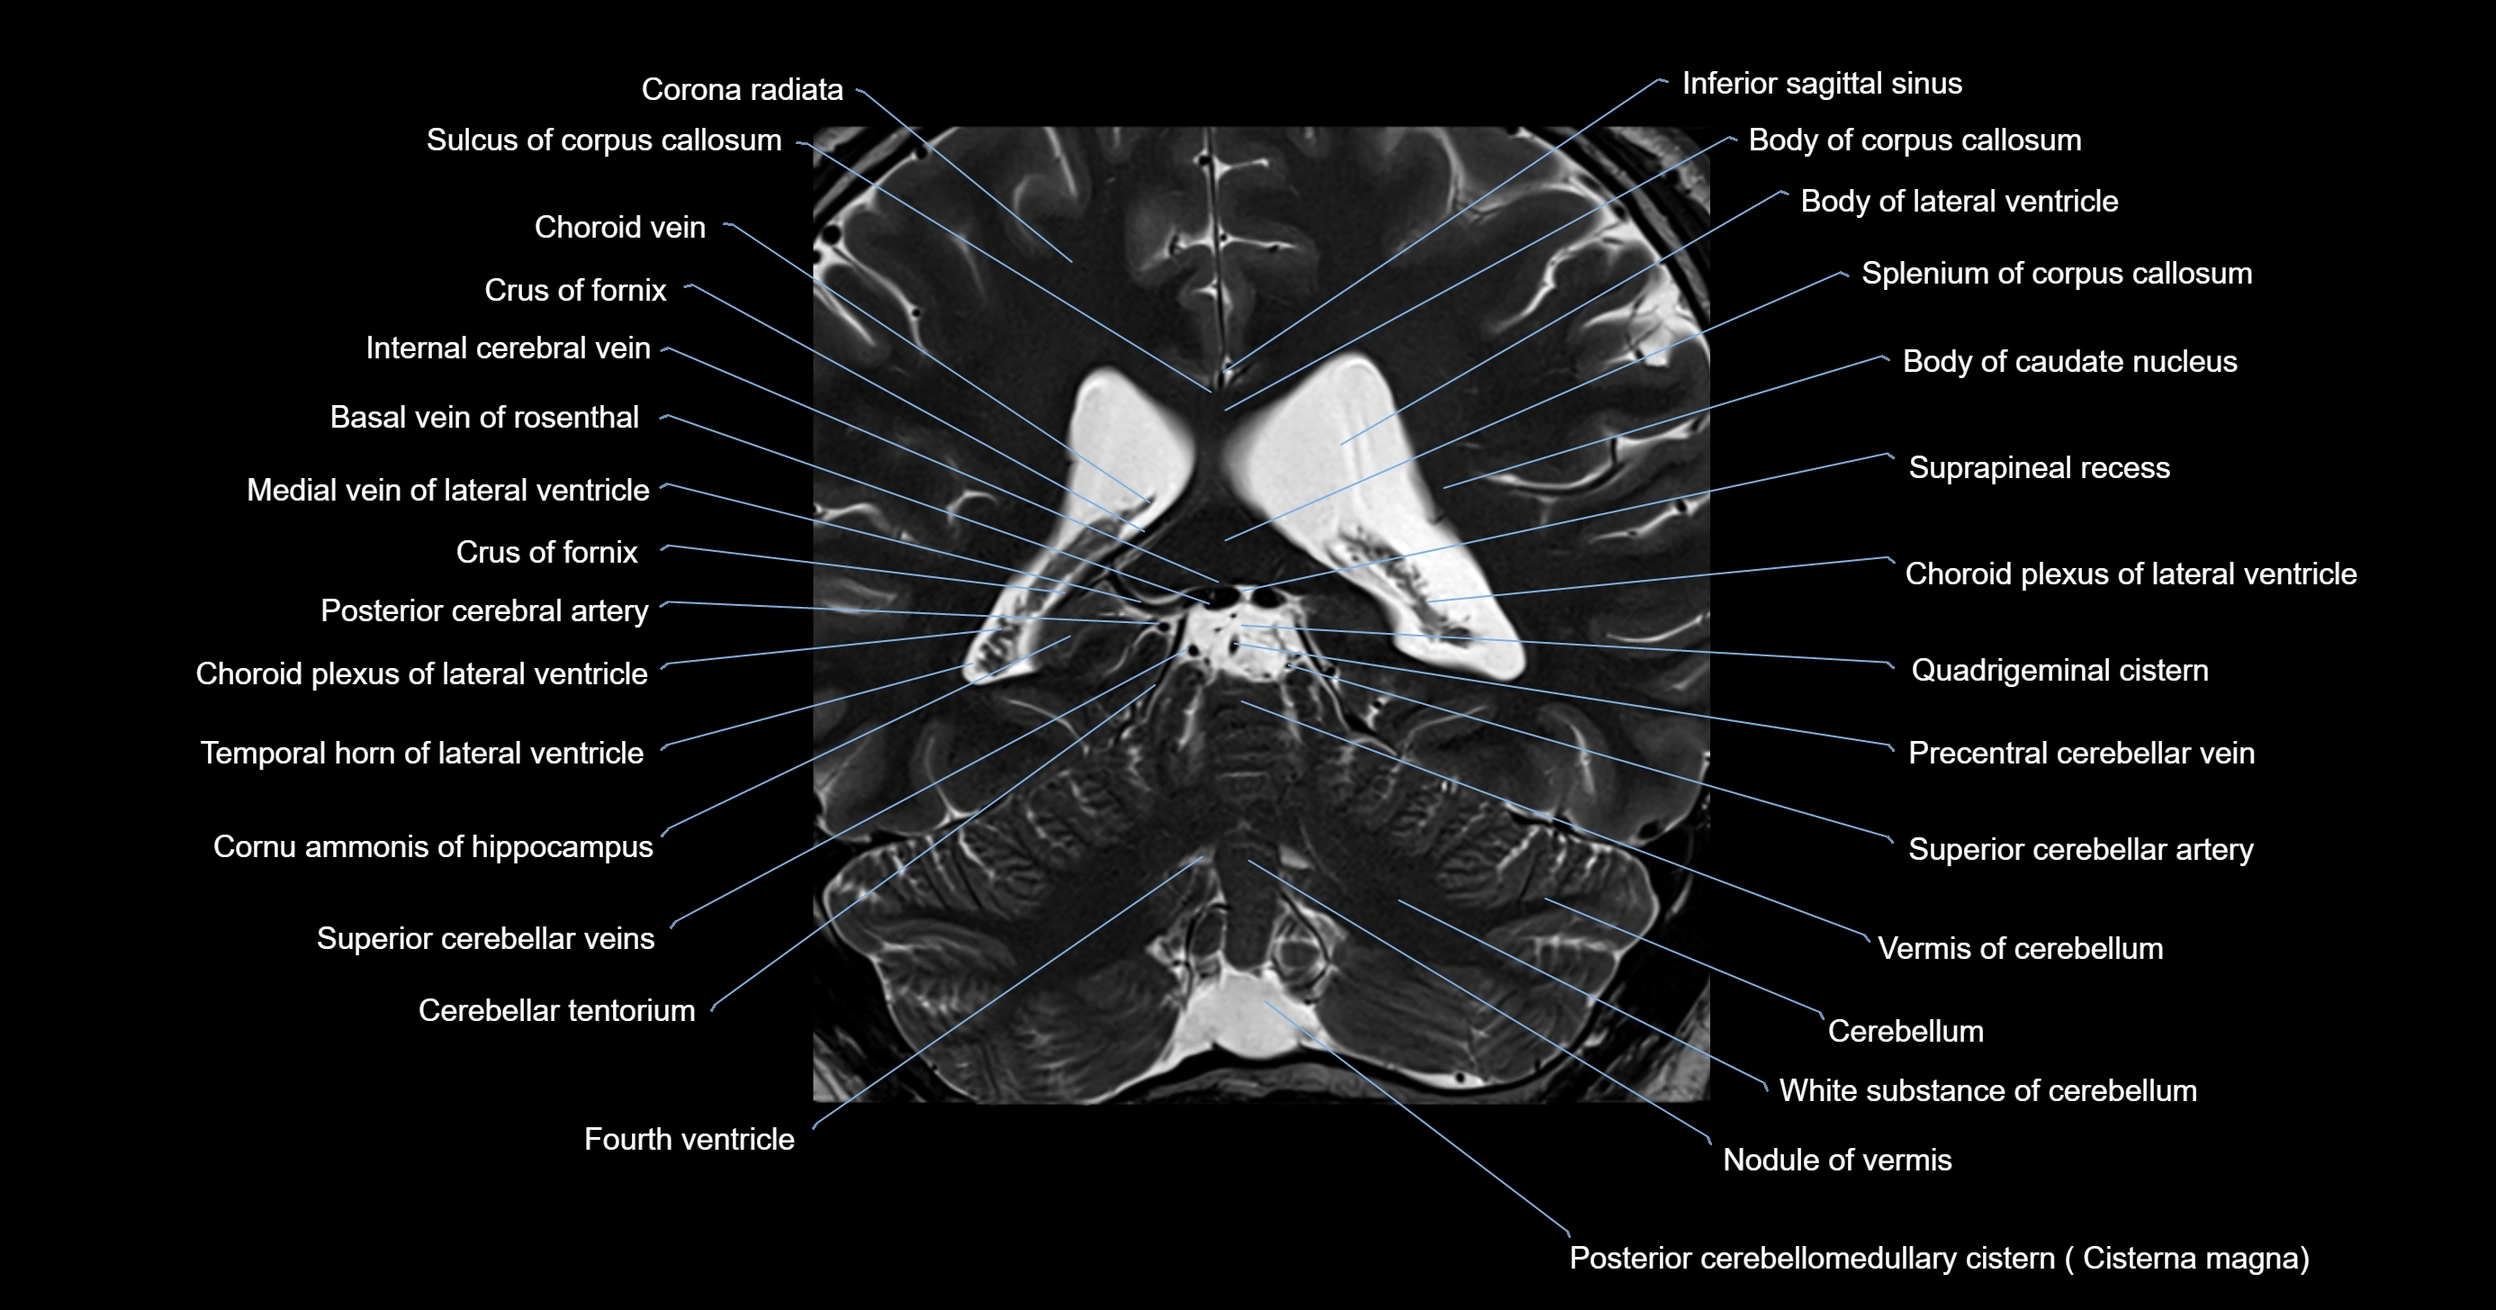

MRI images